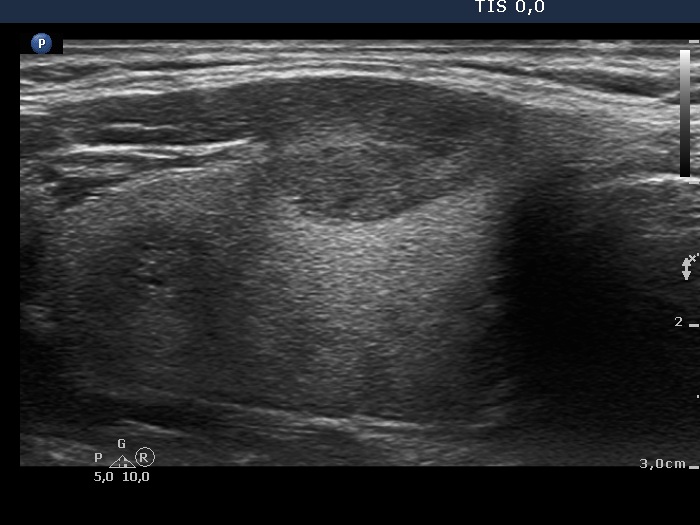

Right lobe, longitudinal scan

Right side of the isthmus, longitudinal scan, enlargement.